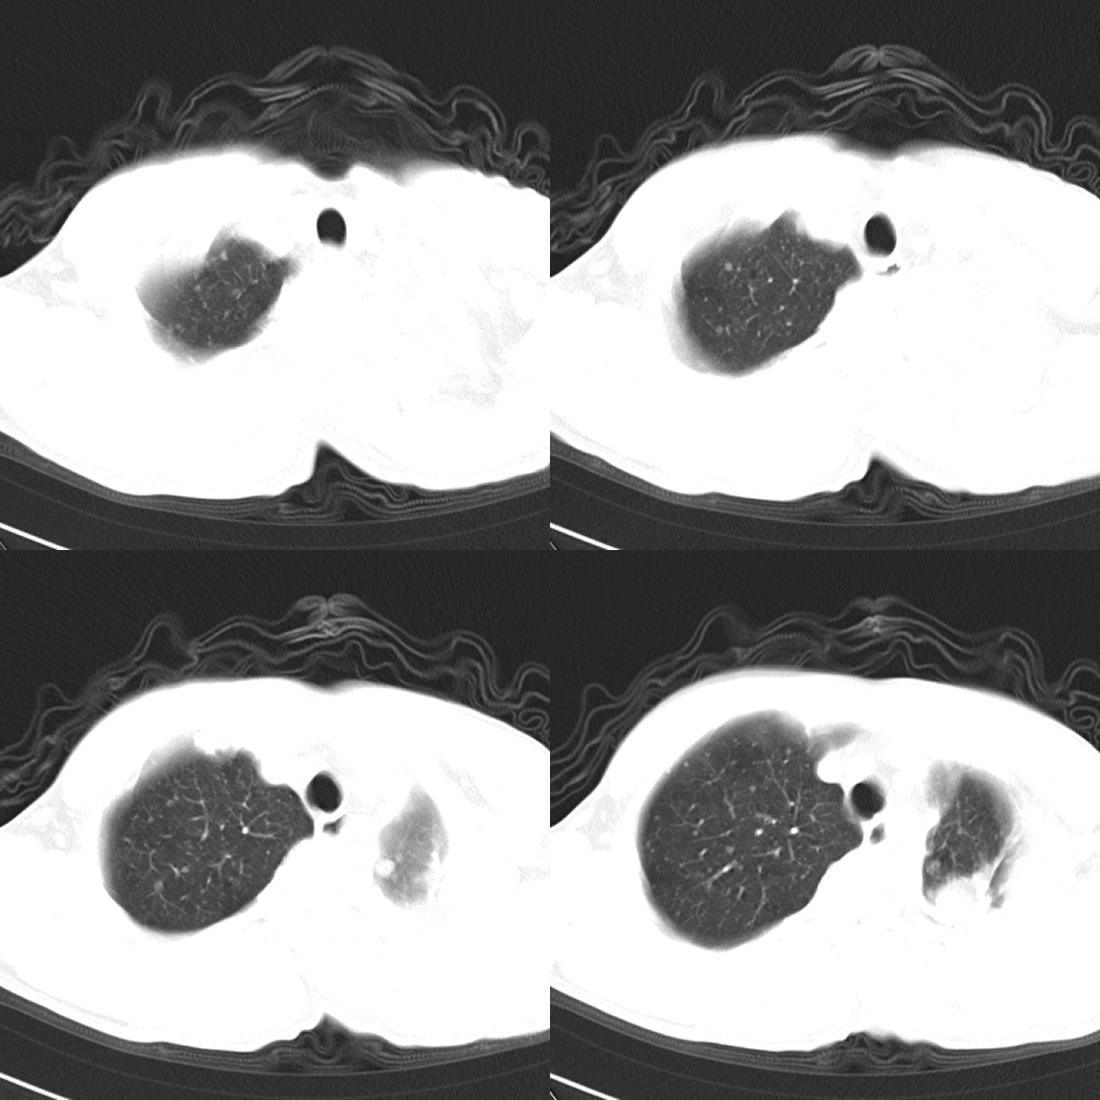

m42y,反复胸背痛数月。无明显的咳嗽、咯痰、咯血症状。

左肺不张 并大量胸腔积液.建议气管镜 除外占位..

左肺上叶周围型肺癌伴肺\\胸膜\\肋骨\\胸椎横突转移,左侧胸腔积液.

左侧椎体、横突、肋骨呈溶骨性破坏,半左侧胸腔中等量积液;左肺尖部可见一肿块影,边界欠清;多考虑恶性骨肿瘤,不除外肺尖部转移性表现可能。

左肺除有肺不张,胸腔积液,尚有斑点、斑片、结节及兔耳征,纤维化等病灶,除考虑除外占位,还应考虑结核所致。。。现在结核病又有泛发趋势。。

左后部肋骨有破坏,应考虑肺癌并转移。。。。